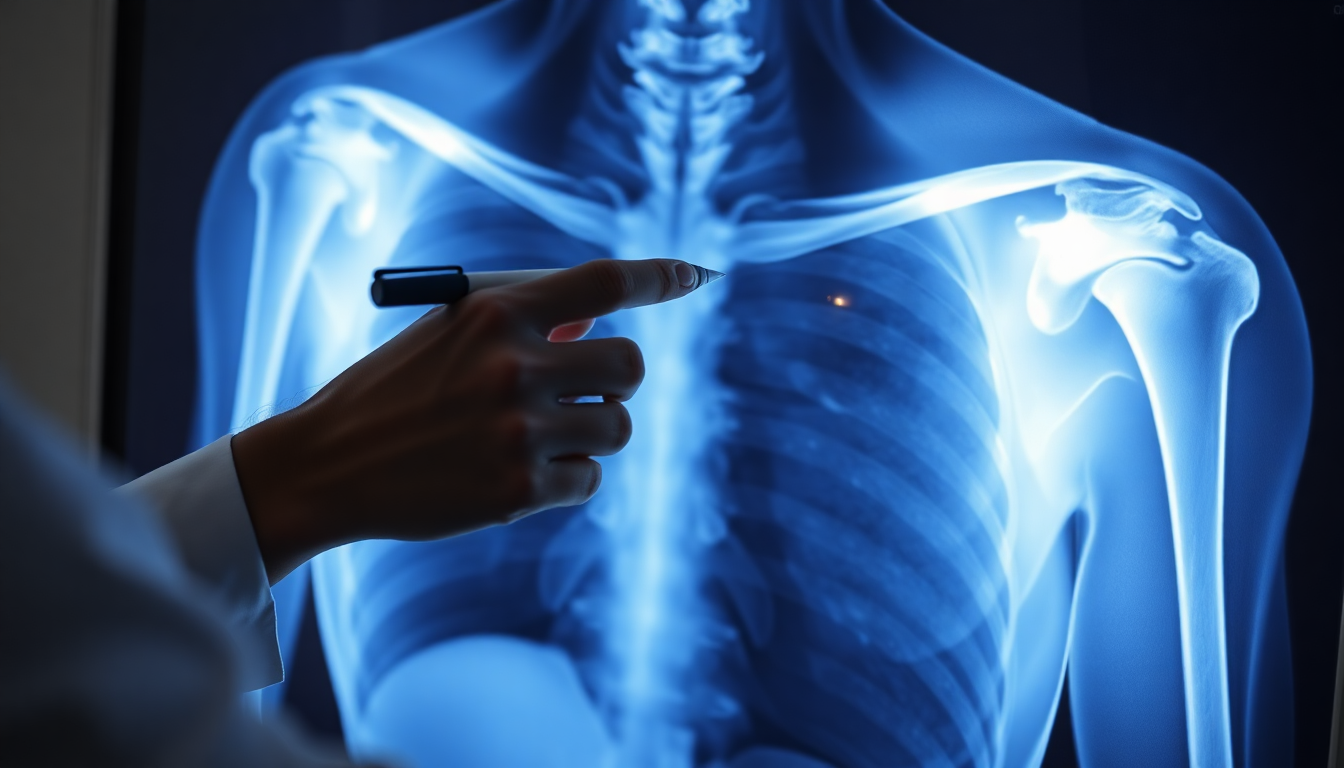

Componentes de la Cintura Escapular

Incluye clavícula, escápula y articulaciones glenohumeral, acromioclavicular y esternoclavicular.

Principios de Evaluación Radiográfica

• Mínimo dos proyecciones ortogonales para una evaluación completa.

• Comparar ambos lados en caso de duda para identificar anomalías.

• Evaluar huesos, alineación, articulaciones y partes blandas en cada estudio.